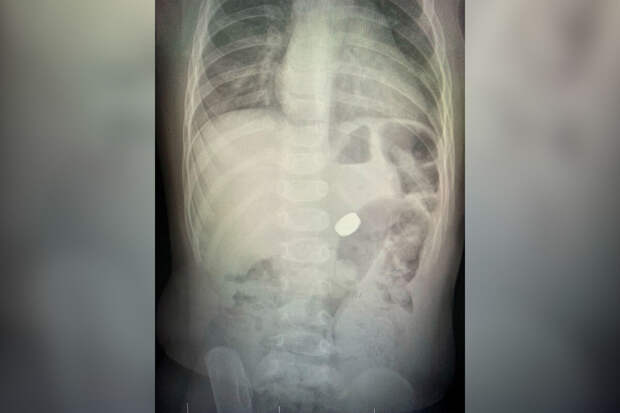

После этого взрослые не досчитались одной батарейки из комплекта.Медики направили младенца на рентген, который показал наличие инородного тела в брюшной полости. С помощью эндоскопа под общим наркозом врачи удалили у ребенка батарейку из желудка. Медики установили, что пациент получил электрохимический ожог желудка.